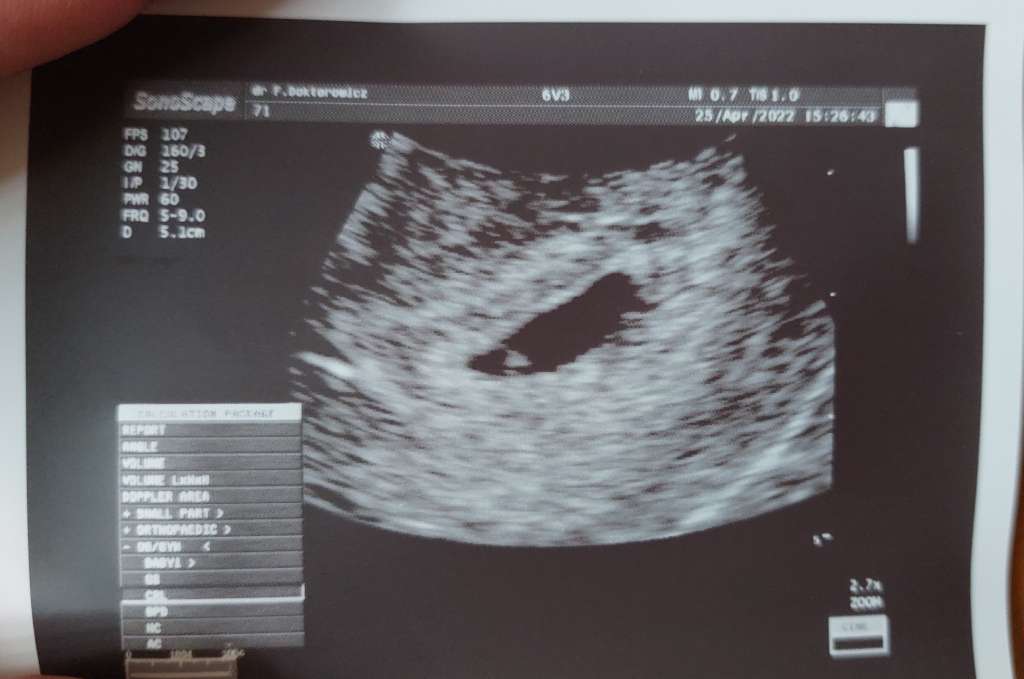

No właśnie, serduszko słychać 6-7 tydzień, na początku jest trochę wolniej i chyba od 8 tyg przyśpiesza 130-150. Ja byłam tydzień temu i nie było serduszka a był początek 6 tyg i narazie czekam sppkojnie i stram się być dobrej myśli.4t i serduszko? Możliwe to jest w ogóle? Ja byłam na wizycie 5+2 i był sam pęcherzyk jeszcze..

wiesz co, osobiście bym poszła na wizytę do innego lekarza, dla świetego spokoju. Według mnie tu musi być blad pomiaru. W 4+6 serduszko nie bije jeszcze(wybijcie mnie z błędu jeśli to wogole możliwe). To tylko sprzęty i wystarczyło ze złe namierzył j wiek wyszedł aż o tyle młodszy.

2mm zarodek jest w 5+5/5+6, także myślę, że to pomyłka o 1 tydzwiesz co, osobiście bym poszła na wizytę do innego lekarza, dla świetego spokoju. Według mnie tu musi być blad pomiaru. W 4+6 serduszko nie bije jeszcze(wybijcie mnie z błędu jeśli to wogole możliwe). To tylko sprzęty i wystarczyło ze złe namierzył j wiek wyszedł aż o tyle młodszy.

właśnie tez na to zwróciłam uwagę. Ale dziwne, ze lekarz jakoś nic na to nie zwrócił uwagi? Myśle, ze sam wie ze w tym tygodniu serduszka nie ma, wiec coś mu pomiar nie poszedł. Ale no nie wchodzę w kompetencje lekarza2mm zarodek jest w 5+5/5+6, także myślę, że to pomyłka o 1 tydz